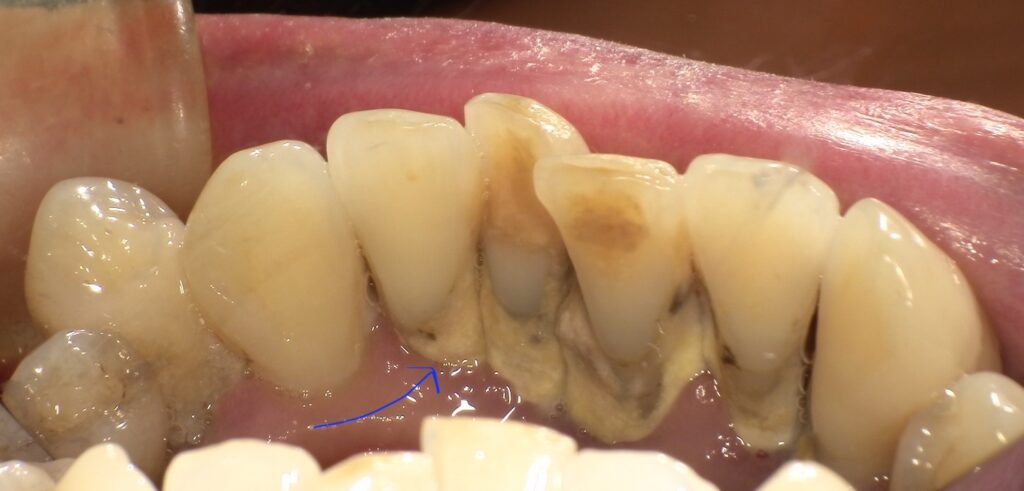

画像の矢印部分が歯肉縁上歯石になります。

歯肉縁上歯石は唾液中のカルシウムやリンが歯垢(プラーク)と

結合し作られます。歯肉縁上歯石がつきますとそのついた部分の歯茎が

清掃できませんので歯肉炎を引き起こします。歯肉縁上歯石は歯科医院での

機械でないと取れません。自分で取れる機会も売っていますが危険ですので

お勧めはしません。